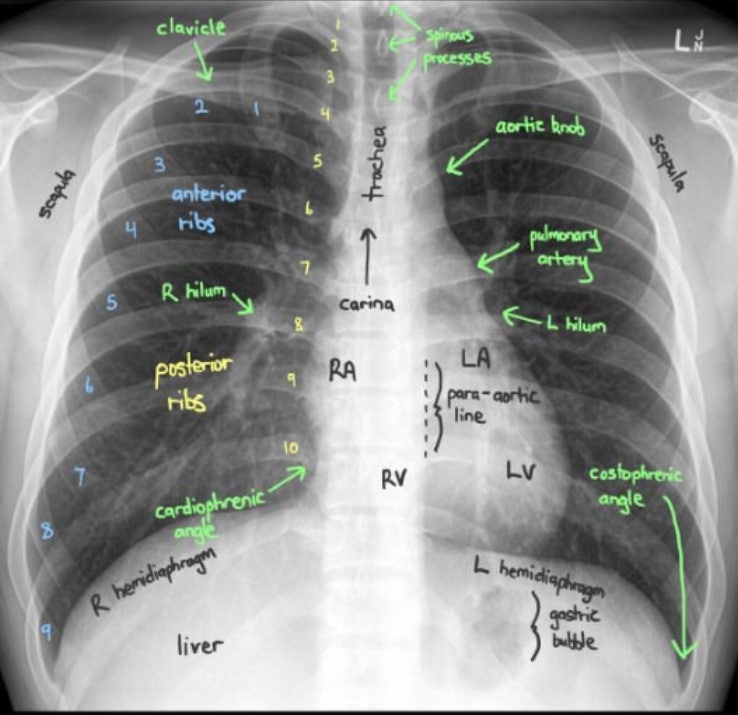

Normal Chest XRay Labelled Anatomy PA View CXR Interpretation Ribs What Organs Are Seen On A Chest X Ray This tutorial covers the trachea,. It can help diagnose conditions such as pneumonia, lung cancer, heart. Find out how to determine the view, quality, and anatomy of the cardiac. It can help your healthcare provider see how well your lungs and heart are working. What Organs Are Seen On A Chest X Ray.